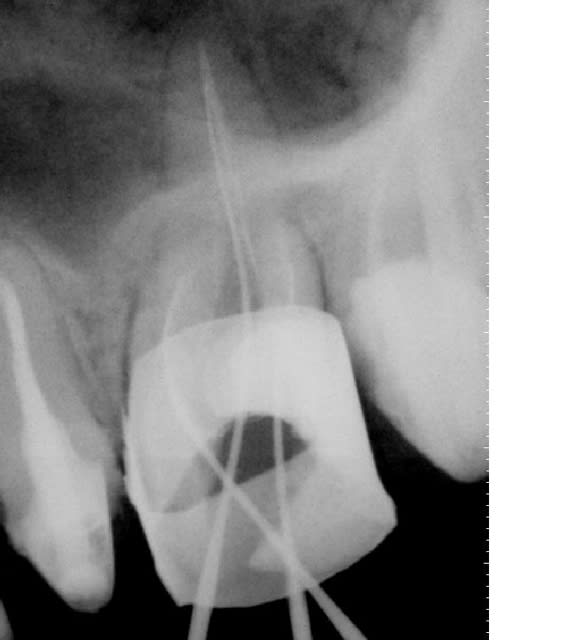

Quand je vois le traitement de Ploc, je trouve qu'il était justifié puisque la dent présente certes une belle lésion périradiculaire, mais a des canaux sans grande anomalie de forme et plutot bien obturés.